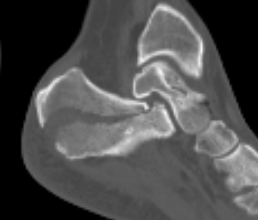

Tongue type

- involve posterior subtalar joint

- secondary fracture line extends posteriorly into calcaneal tuberosity

Imaging